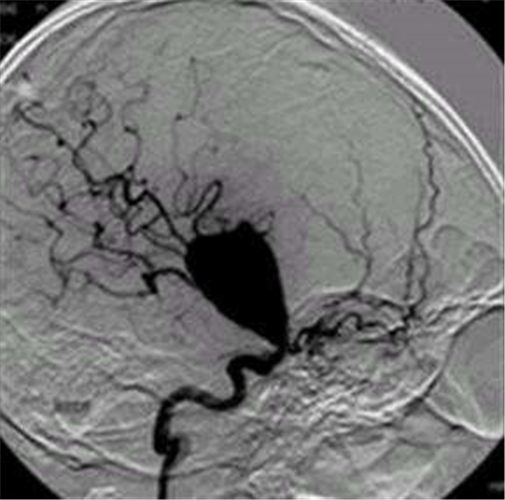

腦供血不足造影

腦供血不足血管造影